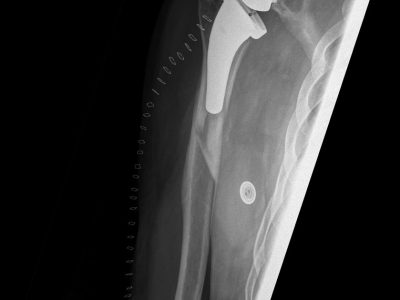

3. Κατάγματα /εξαρθρήματα ώμου και αγκώνα που χρήζουν αντιμετώπισης με Αρθροπλαστική.

Παρακάτω παρατίθενται ακτινογραφίες καταγμάτων του άνω άκρου που αντιμετωπίζονται με εσωτερική οστεοσύνθεση ή επανορθωτική χειρουργική με αρθροπλαστική.